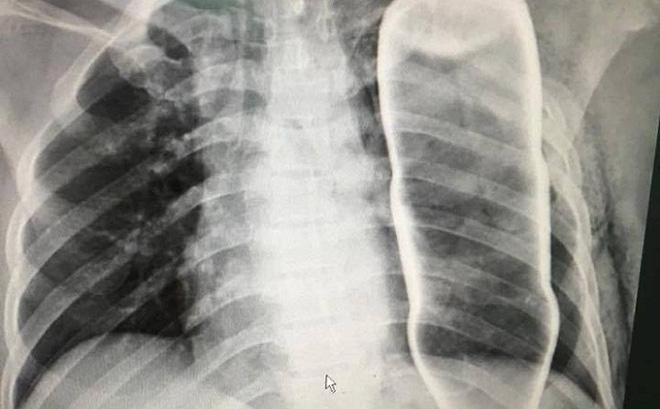

Ngay sau đó, các bác sỹ đã tiến hành chụp X Quang, Citi và vô cùng kinh ngạc khi phát hiện một vỏ chai nước khoáng đang nằm gọn trong ngực của bệnh nhân B.

Sau khi hội chẩn, các y bác sỹ của Bệnh viện Đà Nẵng đã lập tức thực hiện phẫu thuật để lấy vỏ chai ra khỏi lồng ngực bệnh nhân.

Được biết, dù bị vỏ chai to xuyên vào ngực nhưng may mắn nạn nhân chỉ bị gãy 2 xương sườn và không có tổn thương nghiêm trọng nào khác.